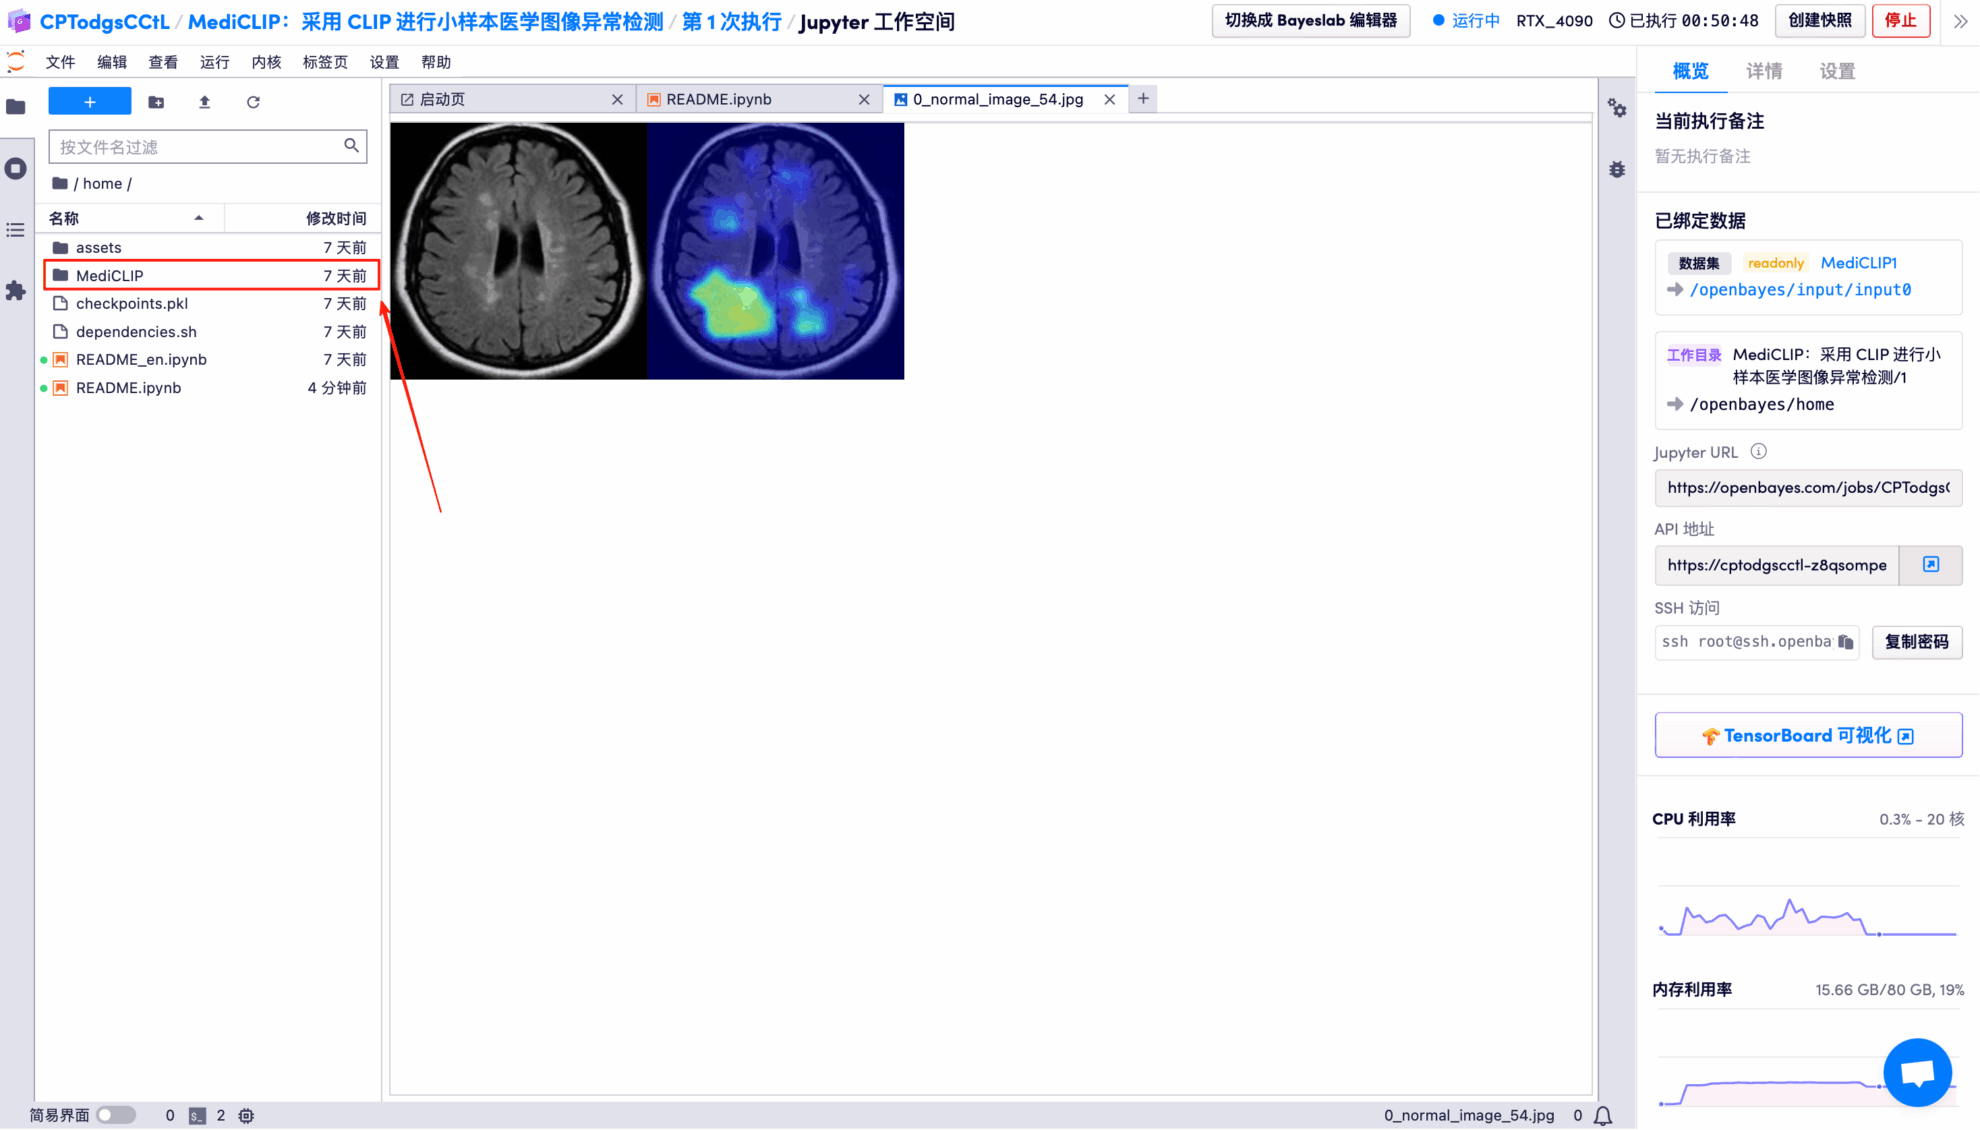

5. Double-click the project name in the left-hand directory to start using it. Note: This tutorial uses a single RTX 4090 GPU. Do not open both the Chinese and English versions of the Notebook at the same time; simply open one. README.ipynb is recommended (the Chinese version is easier to read).

7. MediCLIP model trained on the BrainMRI dataset using 16 support samples.

The model's visual detection results for each test image are saved to the openbayes//home/MediCLIP/vis_result directory by default. The specific location is shown in the figure below:

Randomly open a test result picture, which is clearly and intuitively displayed:

* Left: Original brain image

* Right: Highlighted "abnormal area"